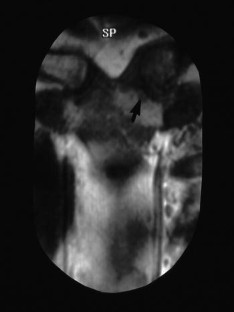

Fig. 4.